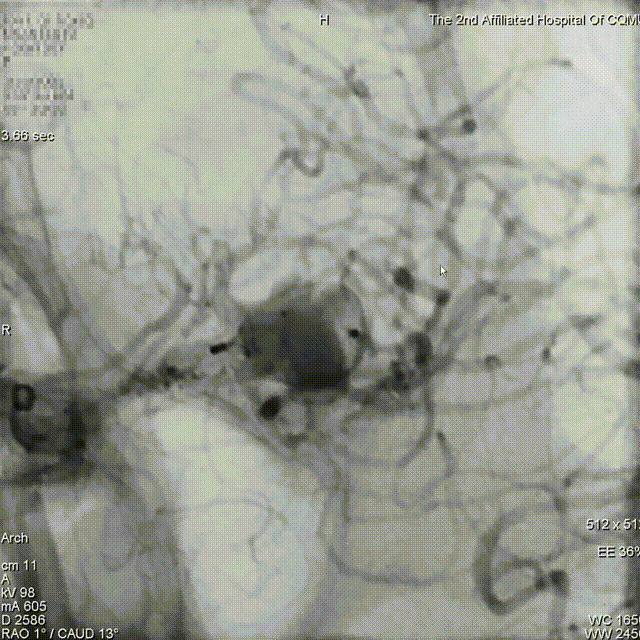

动脉瘤一:基底动脉末端动脉瘤

动脉瘤一:基底动脉末端动脉瘤,由左侧大脑后动脉与左侧小脑上动脉瘤夹角处动脉瘤形成且为不规则状;瘤体上有子囊形成,左侧小脑上动脉从近心端瘤颈处动脉瘤瘤体上发出,动脉瘤与载瘤动脉近直角。

经测量可得动脉瘤宽度平均值为8.88mm,动脉瘤最小高度为7.71mm,瘤颈约为4.03mm。参考尺寸选择表,选择WEB™ SL 10*5,VIA™ 33微导管。

缓慢推出WEB™从种子至萌芽状态,继续向瘤腔内远端缓慢推送WEB™至萌芽至开花间状态;将WEB™和VIA™送至瘤顶,固定WEB™推送杆回撤VIA™,WEB™完全释放。

经造影可见WEB™尺寸合适,贴合瘤壁,小脑上动脉分支,大脑后动脉分支等血流通畅。解脱后,再次造影和Dyna-CT评估,可见动脉瘤瘤腔内有明显造影剂滞留,小脑上动脉瘤显影良好,分支血管血流正常。